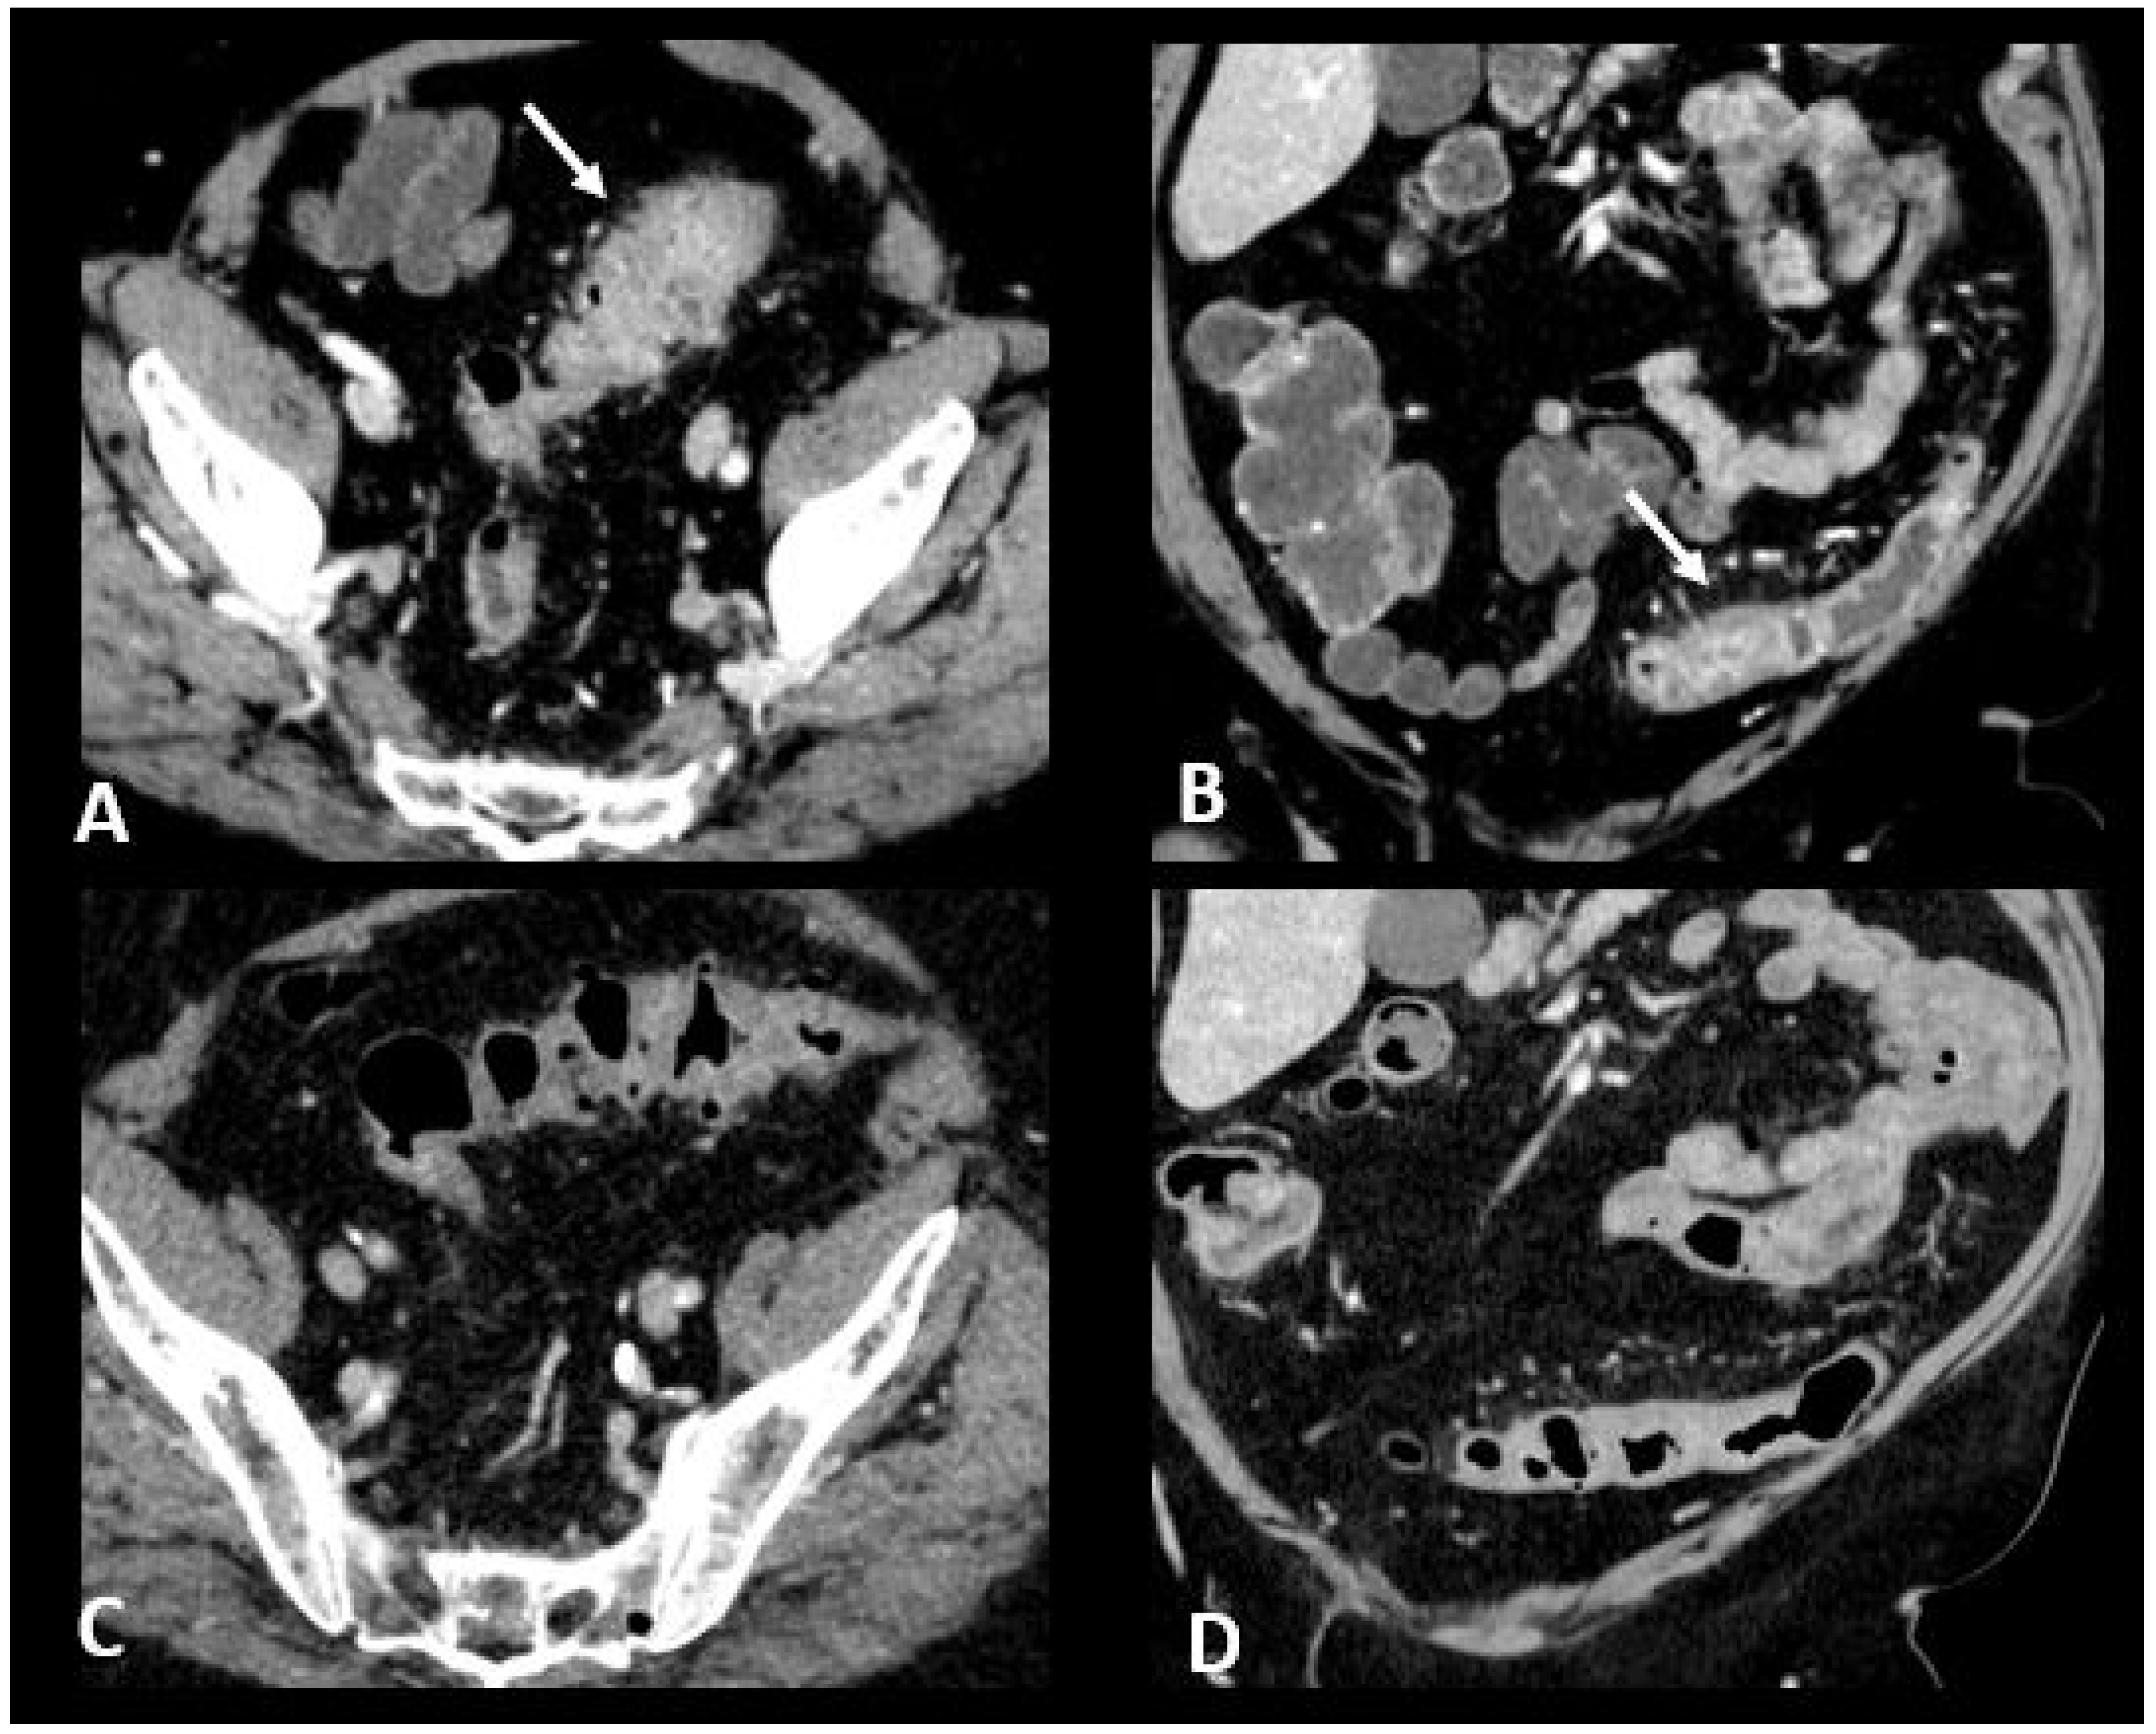

CT is recommended in case of grade 3/4 diarrhea/colitis to assess the extent and severity of colitis. CT protocol includes a single acquisition at the “enteric phase” or “portal venous phase”, meaning around 50 s or 65 s, respectively, after an iodinated contrast agent intravenous injection. Oral contrast agents may be administrated according to the institutional customs. Ir-colitis often exhibits a distinct preference for the distal colon, with the small bowel occasionally affected, typically in conjunction with colitis. A notable imaging feature is the presence of diffuse bowel inflammation combining a bowel wall thickening > 4 mm with mucosal hyperenhancement, congestion of mesenteric vessels, and air-fluid level [24]. Immunotherapy-related colitis may also manifest as segmental colitis. The rectosigmoid region, in particular, tends to be prominently affected, and there is a potential for mimicking symptoms and imaging characteristics of sigmoid diverticulitis. Thickening of the terminal ileum has also been reported [76]. Examples of ir-enterocolitis are shown in Figure 6. PET/CT, when performed for oncologic evaluation, has been reported to be more sensitive than CT scans for early detection of immunotherapy-related entero-colitis which appears as an intestinal heterogeneous, moderate to marked, metabolic activity [24]. However, caution is warranted due to the lack of specificity, especially in patients treated with metformin, where markedly increased non-pathological uptake is frequently observed and can cause complexities in interpretation [77]. Complications such as ischemia, necrosis, hemorrhage, and toxic megacolon can arise as serious and potentially life-threatening consequences during the course of immunotherapy treatment [78]. Severe acute colitis may also result in colonic perforation and death, particularly when there are delays in diagnosis. Previous reports have shown colon perforation in 0.7–1.5% of melanoma patients [79] and 6.6% of renal cell carcinoma patients [80]. In melanoma phase III trials, 0.6–1% of patients died of complications related to ipilimumab-induced enterocolitis [81].

Figure 6.

Immune-related colitis in a patient with a lung epidermoid carcinoma treated with nivolumab + ipilumimab. After 2 cycles of immunotherapy, the patient experienced grade 3 diarrhea. Transverse (A) and coronal (B) CT images show a segmental thickening of the sigmoid mimicking sigmoid diverticulitis (white arrows). The CT images in transverse (C) and coronal sections (D) performed after treatment cessation show a significant regression in the thickening of the sigmoid wall.

As for other irAEs, management depends on gravity [10]. For grade 1, symptomatic approaches including maintaining adequate hydration and diet, as well as the use of cholestyramine, are recommended. In case of a more severe disease, the treatment should be discontinued, and systemic glucocorticoid administration is mandatory. The way of administration and the dose depends on the gravity and tolerability (i.e., fluids, bland diet). Biologic agents such as infliximab and vedolizumab are used sequentially for patients who do not present a response within 3 days of intravenous glucocorticoid therapy. Although both agents have the same efficacy, vedolizumab is linked to a longer time to achieve clinical response but with a shorter duration of glucocorticoid use [82].